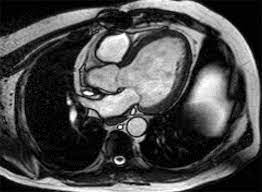

Enter the transformative power of Cardiac MRI—a beacon of hope in the world of cardiac diagnostics. Unlike traditional methods, Cardiac MRI provides a comprehensive look at the heart without the need for invasive procedures, offering clarity with unmatched precision. For Shekhar, this meant a chance to understand his heart's health with a depth that was previously unavailable.

Upon visiting a local diagnostic center, Shekhar underwent a Cardiac MRI that utilized advanced imaging technology to capture detailed images of his heart. The process was seamless, pain-free, and most importantly, accurate. The results revealed early signs of myocardial ischemia, a condition that, if left unchecked, could lead to severe complications. Armed with this knowledge, Shekhar was able to work with his cardiologist to devise a proactive treatment plan, focusing on lifestyle changes and medication to manage his condition effectively.